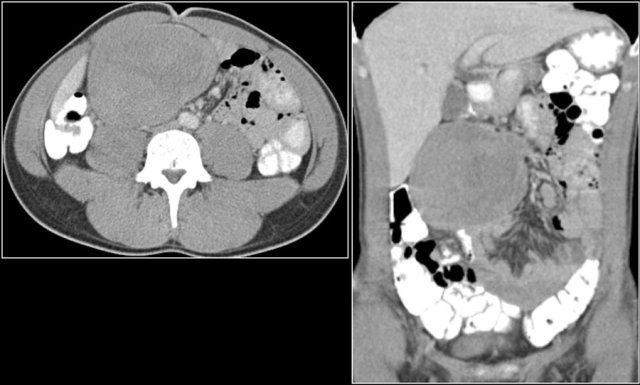

The images show a short obstructing circular mass in the jejunum (yellow arrow) with enlarged lymph node (red arrow).

This proved to be an adenocarcinoma.

Post-contrast T1W-image with fatsat (left) and T2W-image (right) show an obstructing mass in the jejunum with shouldering (arrow).

There is prestenotic dilatation.